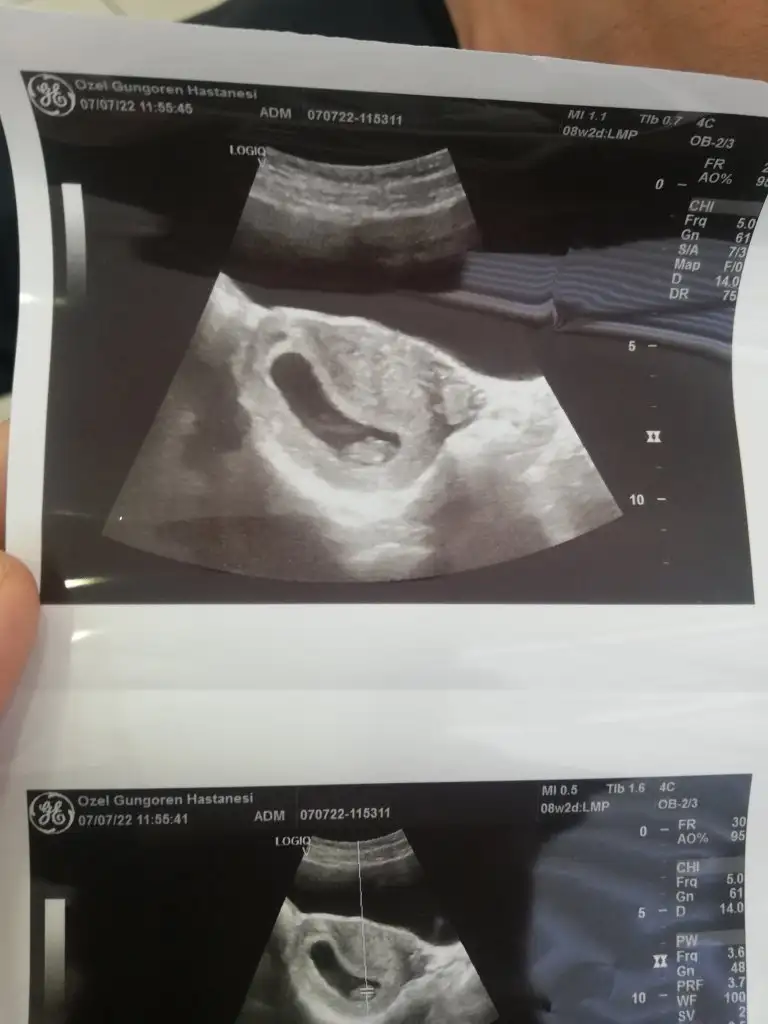

Ikra meyra Ikra meyra Banada bakarmısınız 8+2 karından ultrason

Eklentiler

• IMG_20220707_141730.webp

IMG_20220707_141730.webp

24 KB · Görüntüleme: 43

• IMG_20220707_141737.webp

IMG_20220707_141737.webp

19,6 KB · Görüntüleme: 54